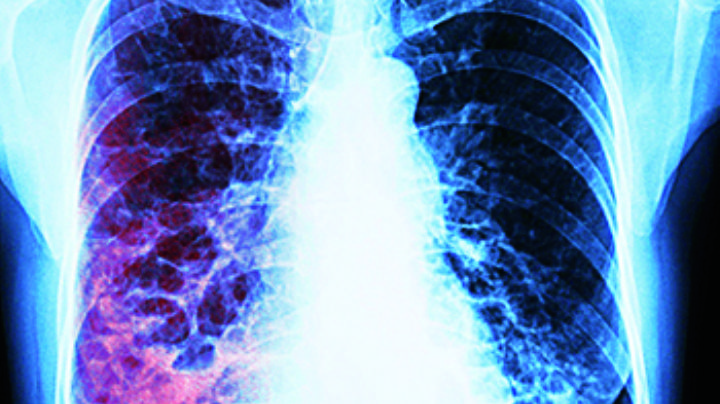

2/9/2025 | Con pruebas de detección y tratamiento oportuno, la tuberculosis se puede prevenir y curar, conoce qué grupos deben extremar precauciones.

16/8/2025 | Autoridades reportan 205 nuevos casos en lo que va de este año, lo que representa un 5% de aumento en comparación con el 2024

24/3/2025 | En 2024 fueron 29 los decesos, cifra por demás alarmante, al ser casi el triple de los 11 fallecimientos registrados en 2020; en 2025 van tres en solo dos meses

9/10/2023 | En apenas nueve meses del presente año han fallecido 12 personas; en todo el 2022 fueron cinco: Jurisdicción Sanitaria